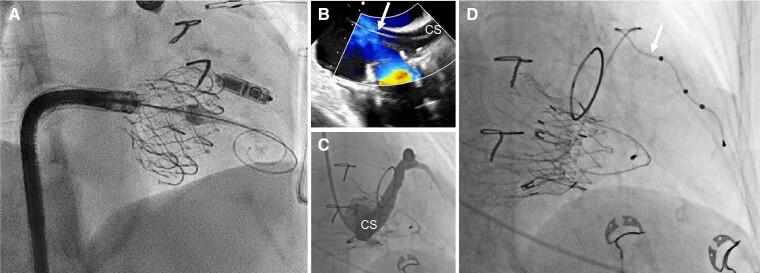

The role of cardiac implantable electronic device (CIED)-related tricuspid regurgitation (TR) is increasingly recognized as an independent clinical entity. Hence, interventional TR treatment options continuously evolve, surgical risk assessment and peri-operative care improve the management of CIED-related TR, and the role of lead extraction is of high interest. Furthermore, novel surgical and interventional tricuspid valve treatment options are increasingly applied to patients suffering from TR associated with or related to CIEDs. This multidisciplinary review article developed with electrophysiologists, interventional cardiologists, imaging specialists, and cardiac surgeons aims to give an overview of the mechanisms of disease, diagnostics, and proposes treatment algorithms of patients suffering from TR associated with CIED lead(s) or leadless pacemakers.